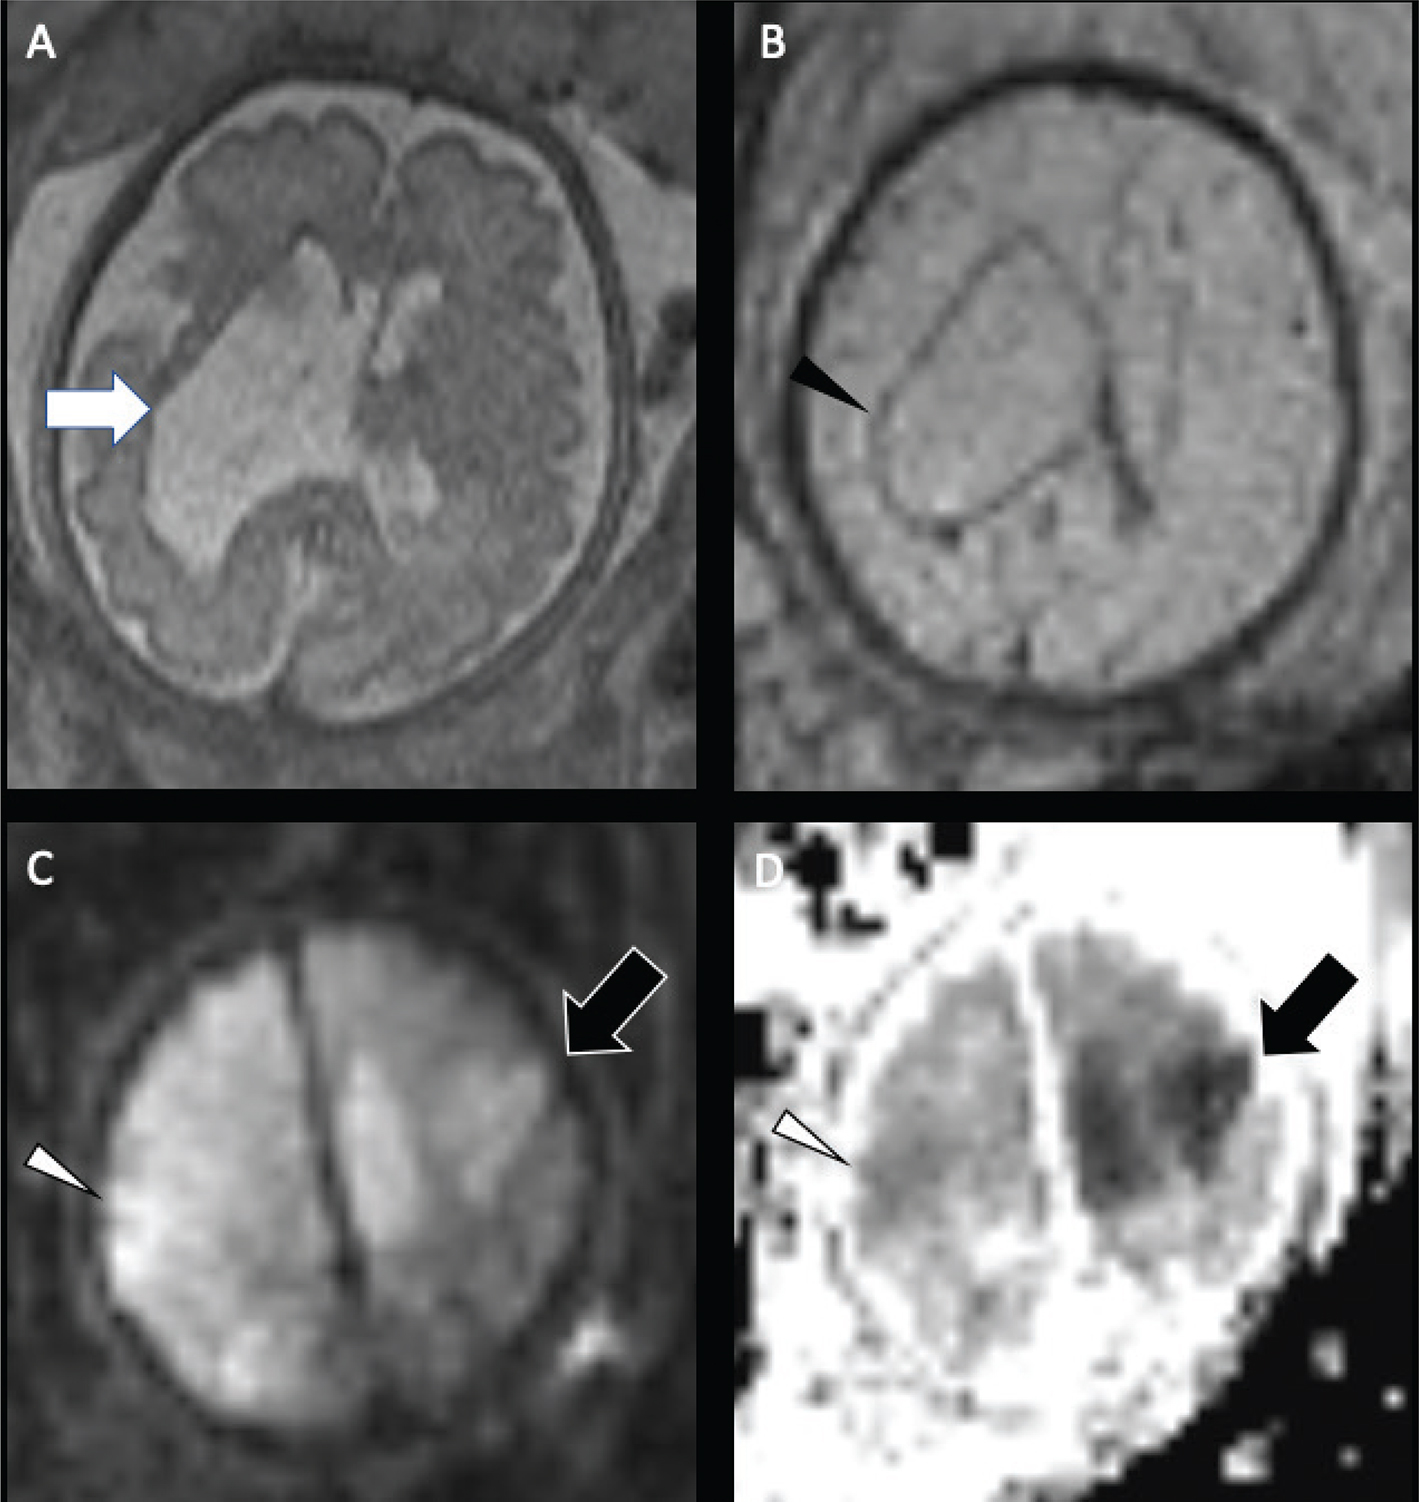

Perfusion imaging is not routinely used in neonatal stroke for technical reasons––dynamic susceptibility contrast-enhanced (DSC) imaging requires a large, generally power-injected contrast bolus and noncontrast arterial spin labeling (ASL) perfusion is technically challenging in neonates in part due to the faster heart rate––and because it does not presently alter patient management in most cases, although paradigms for use of neonatal perfusion are emerging (19). ASL can be used to assess perfusion without the need for intravenous contrast, with pseudocontinuous tagging schemes (pCASL) and ideally flexible prescription of post-label delays preferred (66). Compared to the core and penumbral hypoperfusion seen in older children and adults, neonates often demonstrate hyperperfusion within the region of decreased ADC (Figure 7), with little evidence of adjacent hypoperfusion, which may be related to reperfusion or seizure-associated neuronal hyperexcitability (67). Hypoperfusion may be more common in venous stroke (67).

Fig 7

Figure 7. Neonatal arterial ischemic infarction. DWI (A) demonstrates reduced diffusion in the right PCA territory (white arrow), from acute infarct, as well as the callosal splenium (white arrowhead), representing acute network injury, with increased perfusion on Arterial Spin Labeling (ASL) perfusion (black arrow) (B). Case courtesy of Dr. Tamara Feygin, Department of Radiology, Children’s Hospital of Philadelphia.